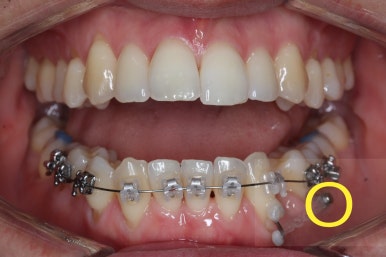

점점 마무리에 가까워지고 있습니다.

화살표는 사랑니인데요. 이 분의 경우 아래 앞니가 1개 없고, 1개를 추가로 뽑아서 윗니 대비 아랫니가 총 2개 모자란거죠.

운이 좋게도 이 분은 사랑니까지 잘 나와있던 상태라 내버려두기 아까워 함께 가지런하게 해주고 사용하실 수 있게 해드렸어요.

부산비수술교정 키다리아저씨치과에서 시행한 이번 치료의 결과입니다.

옆모습이 주걱턱 느낌이 많이 없어졌고 볼록하던 아랫입술도 뒤로 들어갔어요. 앞니가 거꾸로 물리지 않게 되어 웃거나 말하는 모습도 자연스러워졌어요.

아랫니 갯수가 모자라고 중앙이 맞지 않았고 짝이 안맞는 상황이었으나 비교적 잘 마무리를 했어요.

거꾸로 물리는 상황이 개선되었기 때문에 앞니나 어금니의 교합은 이전과 비교할 수 없을만큼 좋아졌지요.